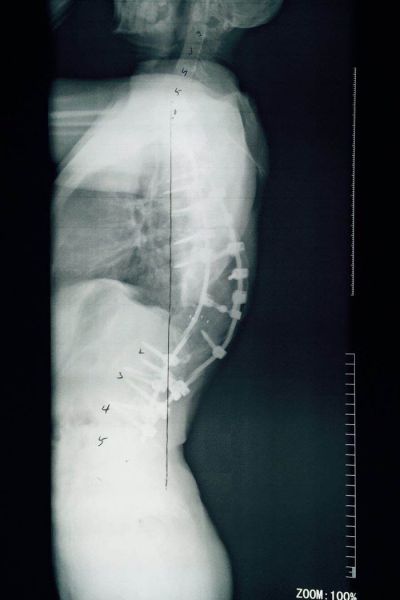

患者于4月21日在全麻下行脊柱后路固定、截骨、矫形、植骨融合术,手术历时12个小时,过程基本顺利,完整达到手术目的。后经过一个多月的积极神经康复锻炼,患者目前基本恢复。患者妈妈激动的说:“孩子长高了,现在和我一样高了,背也直了!”。而且经过术后评估检测,患者伤口一级愈合,身高增长7cm,剃刀背高度下降8cm,双肩等高,躯干已基本平衡,脊柱畸形得到满意矫正,目前患者及家属已经满意出院。